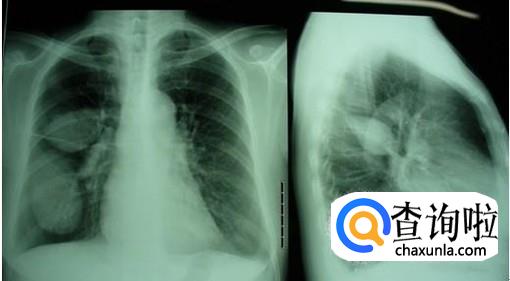

第一种是原发性肺结核,这是原结核杆菌感染导致的原发性结核病,这种结核病更多见于小孩儿,青年和老年人很少见。

第二种是血行播散型肺结核,这是一类病情很危重的结核病了,由结核杆菌干酪样变影响到血源而引起的。

这三种是继发性肺结核,这种会出现以增殖病变为主、浸润病变为主、干酪病变为主或以空洞为主等多种病理改变。

最后是结核性胸膜炎,是结核杆菌直接侵袭胸膜导致胸膜功能受损,进而引发炎症而导致的结核病。